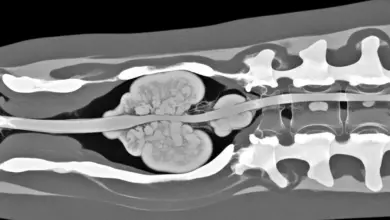

Quando há dúvida, a curva parece rígida, existe dor importante ou quando se quer medir a gravidade, a radiografia em perfil é o exame básico.

Ela permite calcular o ângulo de Cobb e procurar sinais que sugerem alterações estruturais.

Tomografia e ressonância não são rotina na cifose postural. Elas são úteis quando há suspeita de causa congênita, trauma, sintomas neurológicos ou outras condições associadas.